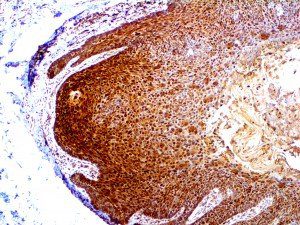

The first cytokines released are interleukin 1β (IL-1β) and tumor necrosis factor-α (TNF-α), which attract a variety of circulating white blood cells (WBCs) to the infection site, including neutrophils, monocytes, macrophages, and natural killer (NK) cells. This response, along with the antipathogenic chemicals released by these cells (i.e., complement), comprise the innate immune response. These cells directly attack the invading pathogen and also release additional cytokines, chief among them interleukin-1 and 6 (IL-6). IL-6 is essential for invoking the adaptive immune response, which calls T-cells, B-cells, and T helper (Th) cells to the infection site. IL-6 also stimulates further recruitment, proliferation and activation of macrophages.

It is the ICU physician who is most likely to witness one of the deadliest manifestations of the abnormal immunological response, the cytokine storm syndrome (CSS). This response is also referred to by some as the cytokine release syndrome (CRS). CSS is characterized by continuous activation and expansion of macrophage and lymphocyte populations, which secrete large amounts of cytokines, causing the cytokine storm. This massive cytokine release is akin to hemophagocytic lymphohistiocytosis (HLH) disease, a syndrome characterized by initial unchecked and persistent activation of cytotoxic T lymphocytes and NK cells.